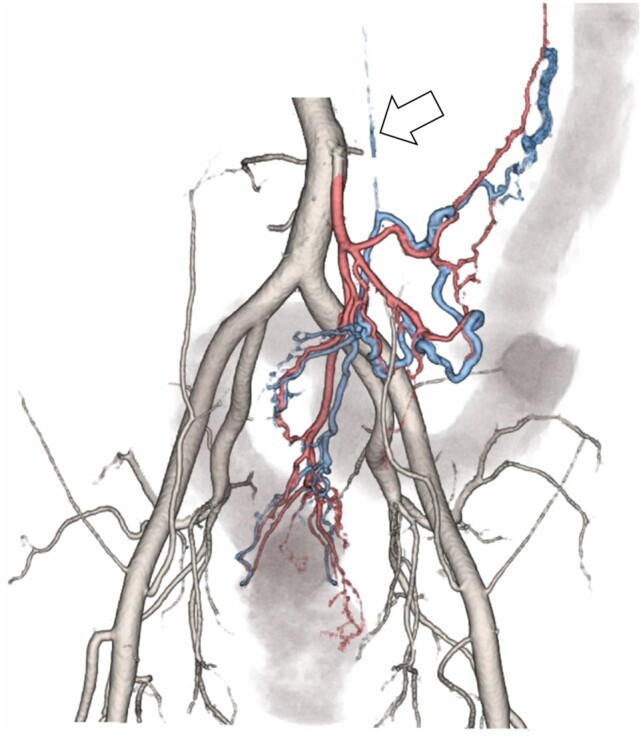

A 44-year-old man presented with a chief complaint of constipation. Initial contrast-enhanced CT showed extensive bowel wall thickening, mainly in the left colon, with a thin cord-like inferior mesenteric vein (IMV), in contrast to ectatic mesenteric venous branches, suggesting bowel ischaemia owing to venous stasis. One month later, at the time of symptom exacerbation, CT angiography showed a cord-like IMV and ectatic mesenteric venous branches with early enhancement, suggesting the presence of an arteriovenous fistula (AVF). Owing to the progression of bowel ischaemia and necrosis with peritonitis, emergency surgery was performed. Surgical specimens showed focal myointimal hyperplasia of the proximal mesenteric veins in both ischaemic and non-ischaemic lesions of the resected colon, thus leading to the diagnosis of idiopathic myointimal hyperplasia of mesenteric veins (IMHMV) when combined with the clinical and imaging findings. IMHMV is a bowel ischaemic disease caused by non-thrombotic venous obstruction that requires bowel resection and has been suggested to be associated with AVF. Cord-like IMV and AVF in the mesentery are important CT findings that characterize IMHMV. CT angiography is useful in diagnosing IMHMV.

一名 44 岁男子以便秘为主诉就诊。最初的造影剂增强 CT 显示肠壁广泛增厚,主要位于左侧结肠,肠系膜下静脉(IMV)呈细绳状,肠系膜静脉分支异位,表明由于静脉瘀血导致肠缺血。一个月后,症状加重时,CT 血管造影显示肠系膜下静脉(IMV)呈条索状,肠系膜静脉分支异位且早期增强,提示存在动静脉瘘(AVF)。由于肠道缺血坏死并伴有腹膜炎,医生对患者进行了紧急手术。手术标本显示,在切除的结肠缺血和非缺血病灶中,肠系膜近端静脉均有局灶性肌腱增生,因此结合临床和影像学检查结果,诊断为特发性肠系膜静脉肌腱增生症(IMHMV)。IMHMV是一种由非血栓性静脉阻塞引起的肠缺血性疾病,需要切除肠道,并被认为与动静脉瘘有关。索状 IMV 和肠系膜中的动静脉瘘是 IMHMV 的重要 CT 发现特征。CT 血管造影有助于诊断 IMHMV。